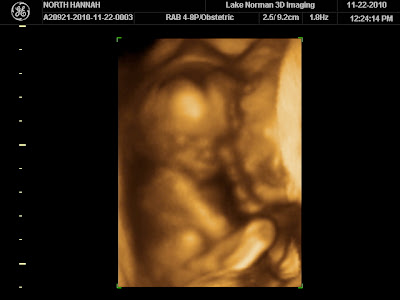

I am having a baby

GIRL

oh my goodness, how i did not think i would be saying that. i don't know how we got so 100% positive that we were having a boy, when there was no way to know, and we had a 50/50 chance either way, but we sure were positive.

now we are still getting used to the idea--no, the reality, of this beautiful little girl soon coming into all of our lives. i can hardly wait to see her face, to hold her hand. to watch my husband turn to absolute mush, and my son blossom into the big, loving, protective brother that he was born to be.

she is still very small (17 weeks), but here are some pictures of the video that we got to watch of her.